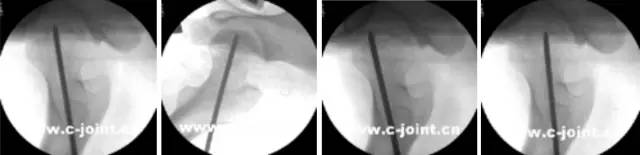

开展关节镜下交叉韧带单、双股解剖重建技术、膝关节多韧带损伤的一期修复重建术、半月板缝合技术、骨软骨移植技术、同种异体移植治疗交叉韧带损伤、双隧道重建交叉韧带、肩关节镜下肩袖修补和SLAP损伤修补术,及肘、踝、腕、髋关节镜术。专业运动员伤病诊治技术、股骨髋臼撞击综合症、股骨头坏死阶梯治疗技术、骨软骨移植技术。

关节镜清理、软骨移植修复

小孔径多孔道低钻速钻孔减压